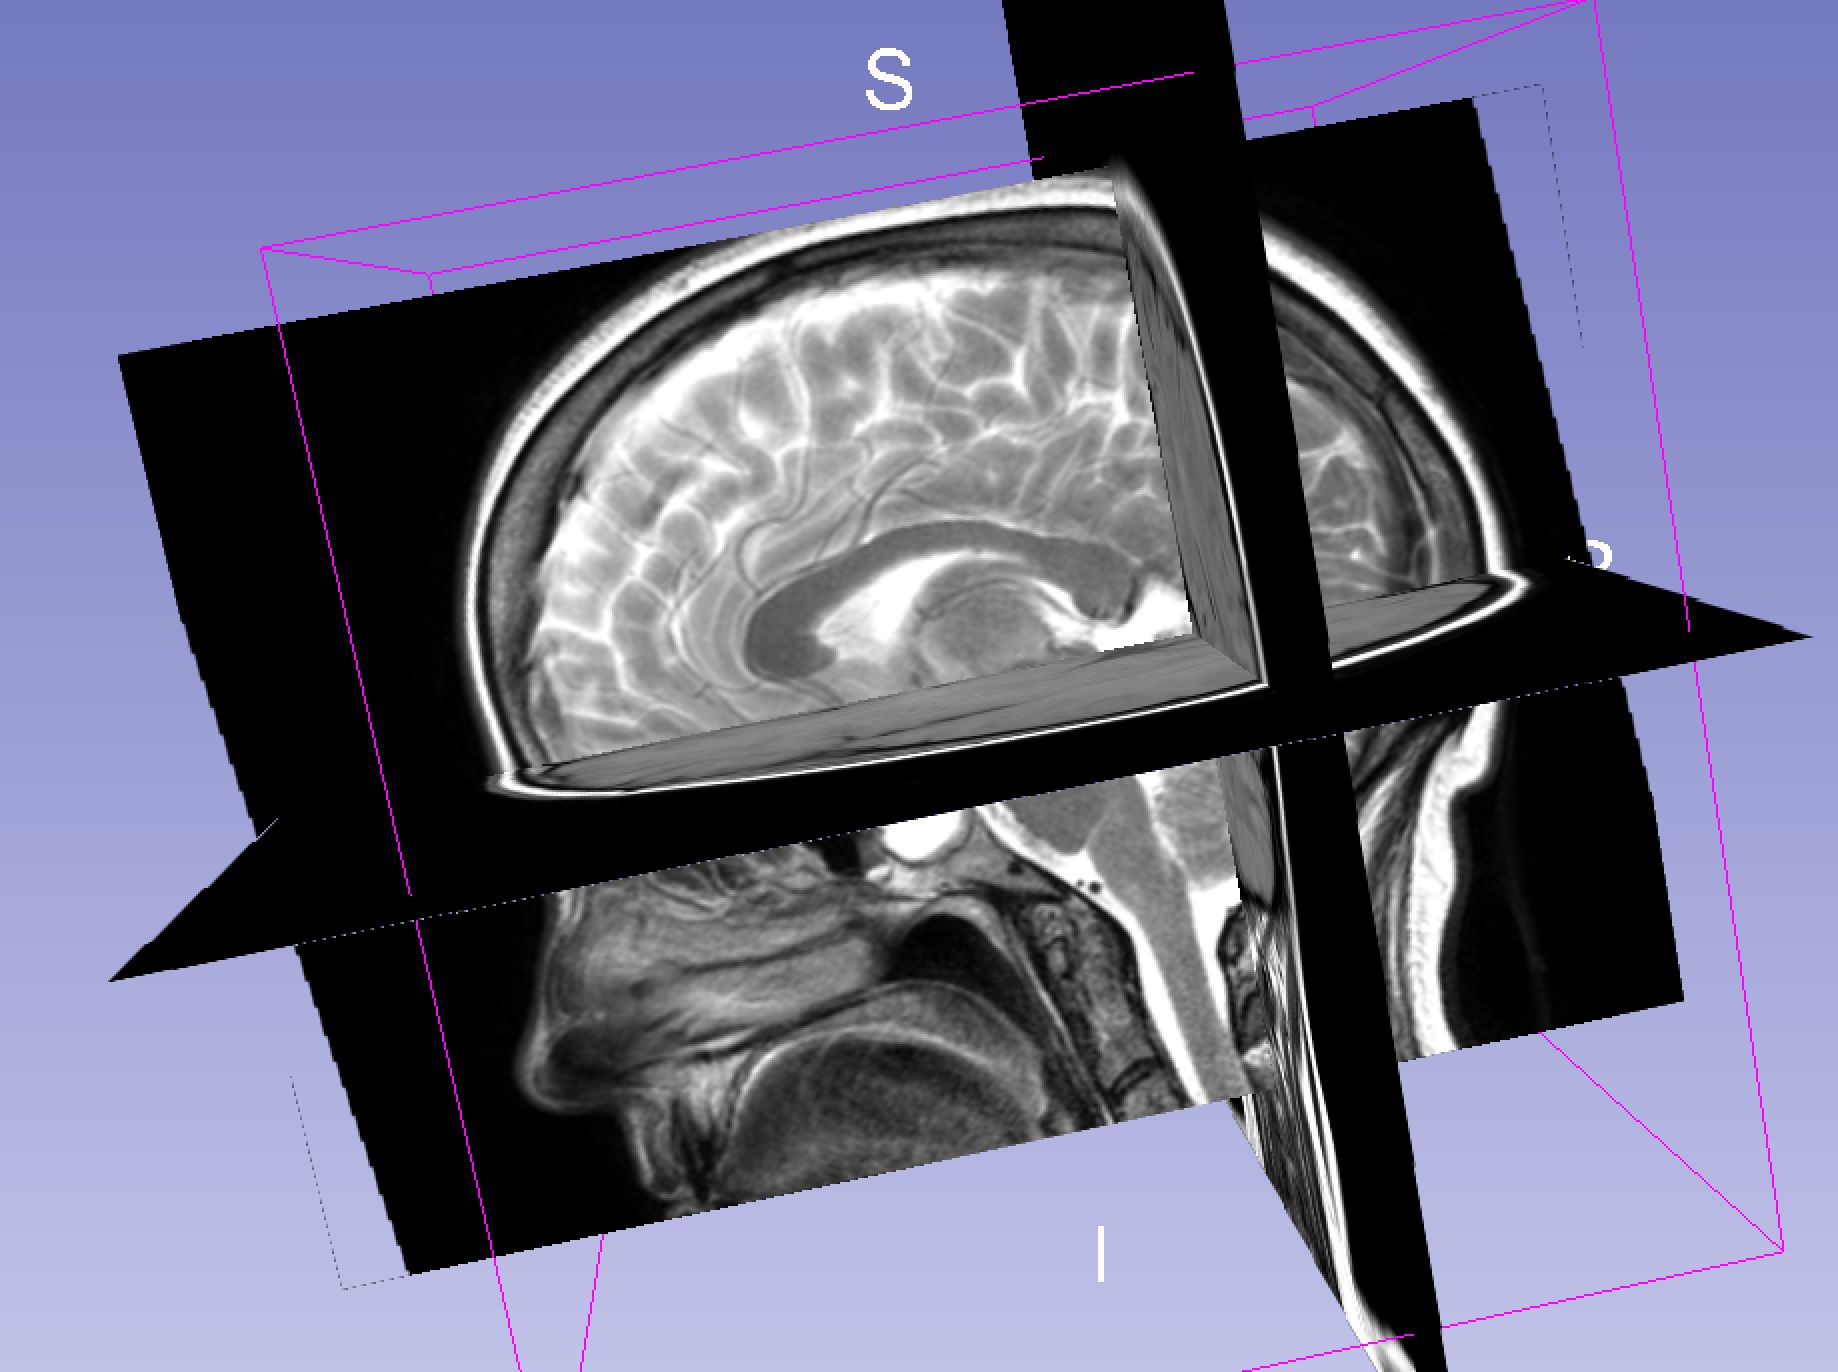

I have an MRI scan of my brain because some doctors wanted a closer look at it. Either I am a raving lunatic, or because I have a remarkable brain. One – or both.

- saggital

Anyway – 3D imaging are basically slices stacked on top of / next to each other. Instead of pixels, they are three-dimentional voxels. Not super important.

The point though, is that this is done in three axes: axial, saggital, coronal. So you can generate a 3D model that have three axes to average from, instead of one – meaning that the 3D model will not look like it was built from lego. As it would, if it only was one axis. I swear, i will 3D-print my brain when I get my head around the software.

Usually, these files are viewed in sequence, one axis at a time – i don’t think there is any medical reason for building models of an entire brain. I imagine that making 3D digital or physical models of various structures inside the brain, or tumors and such, would make sense.